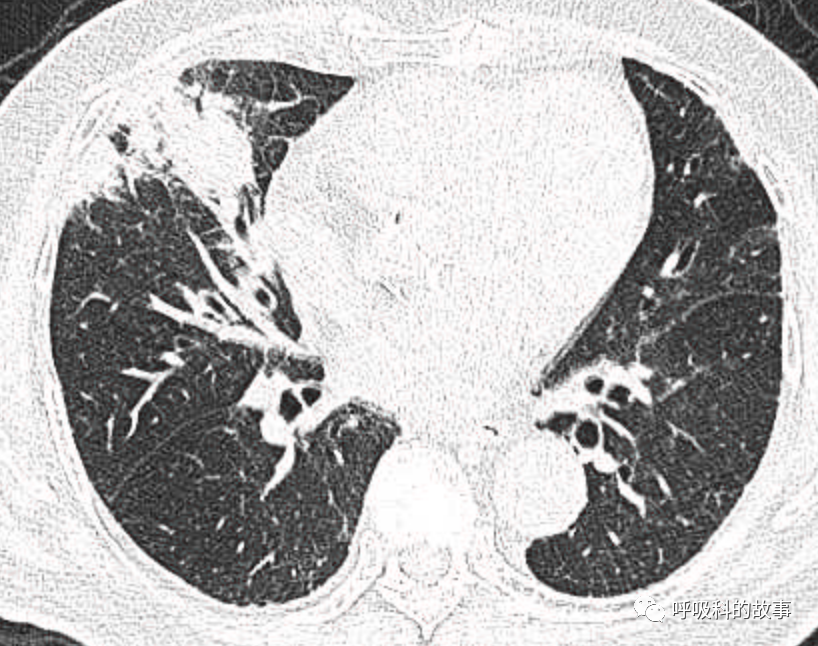

可是就在今年初,患者曾住在某院某科室,因为其他内科疾病住院。当时肺部CT也发现了在右中叶内侧段的高密度实变影,由于影像很类似肺炎,因此当成肺炎治疗。

图12-14:该患者各个角度的影像图像

(上下滑动查看全部图片)